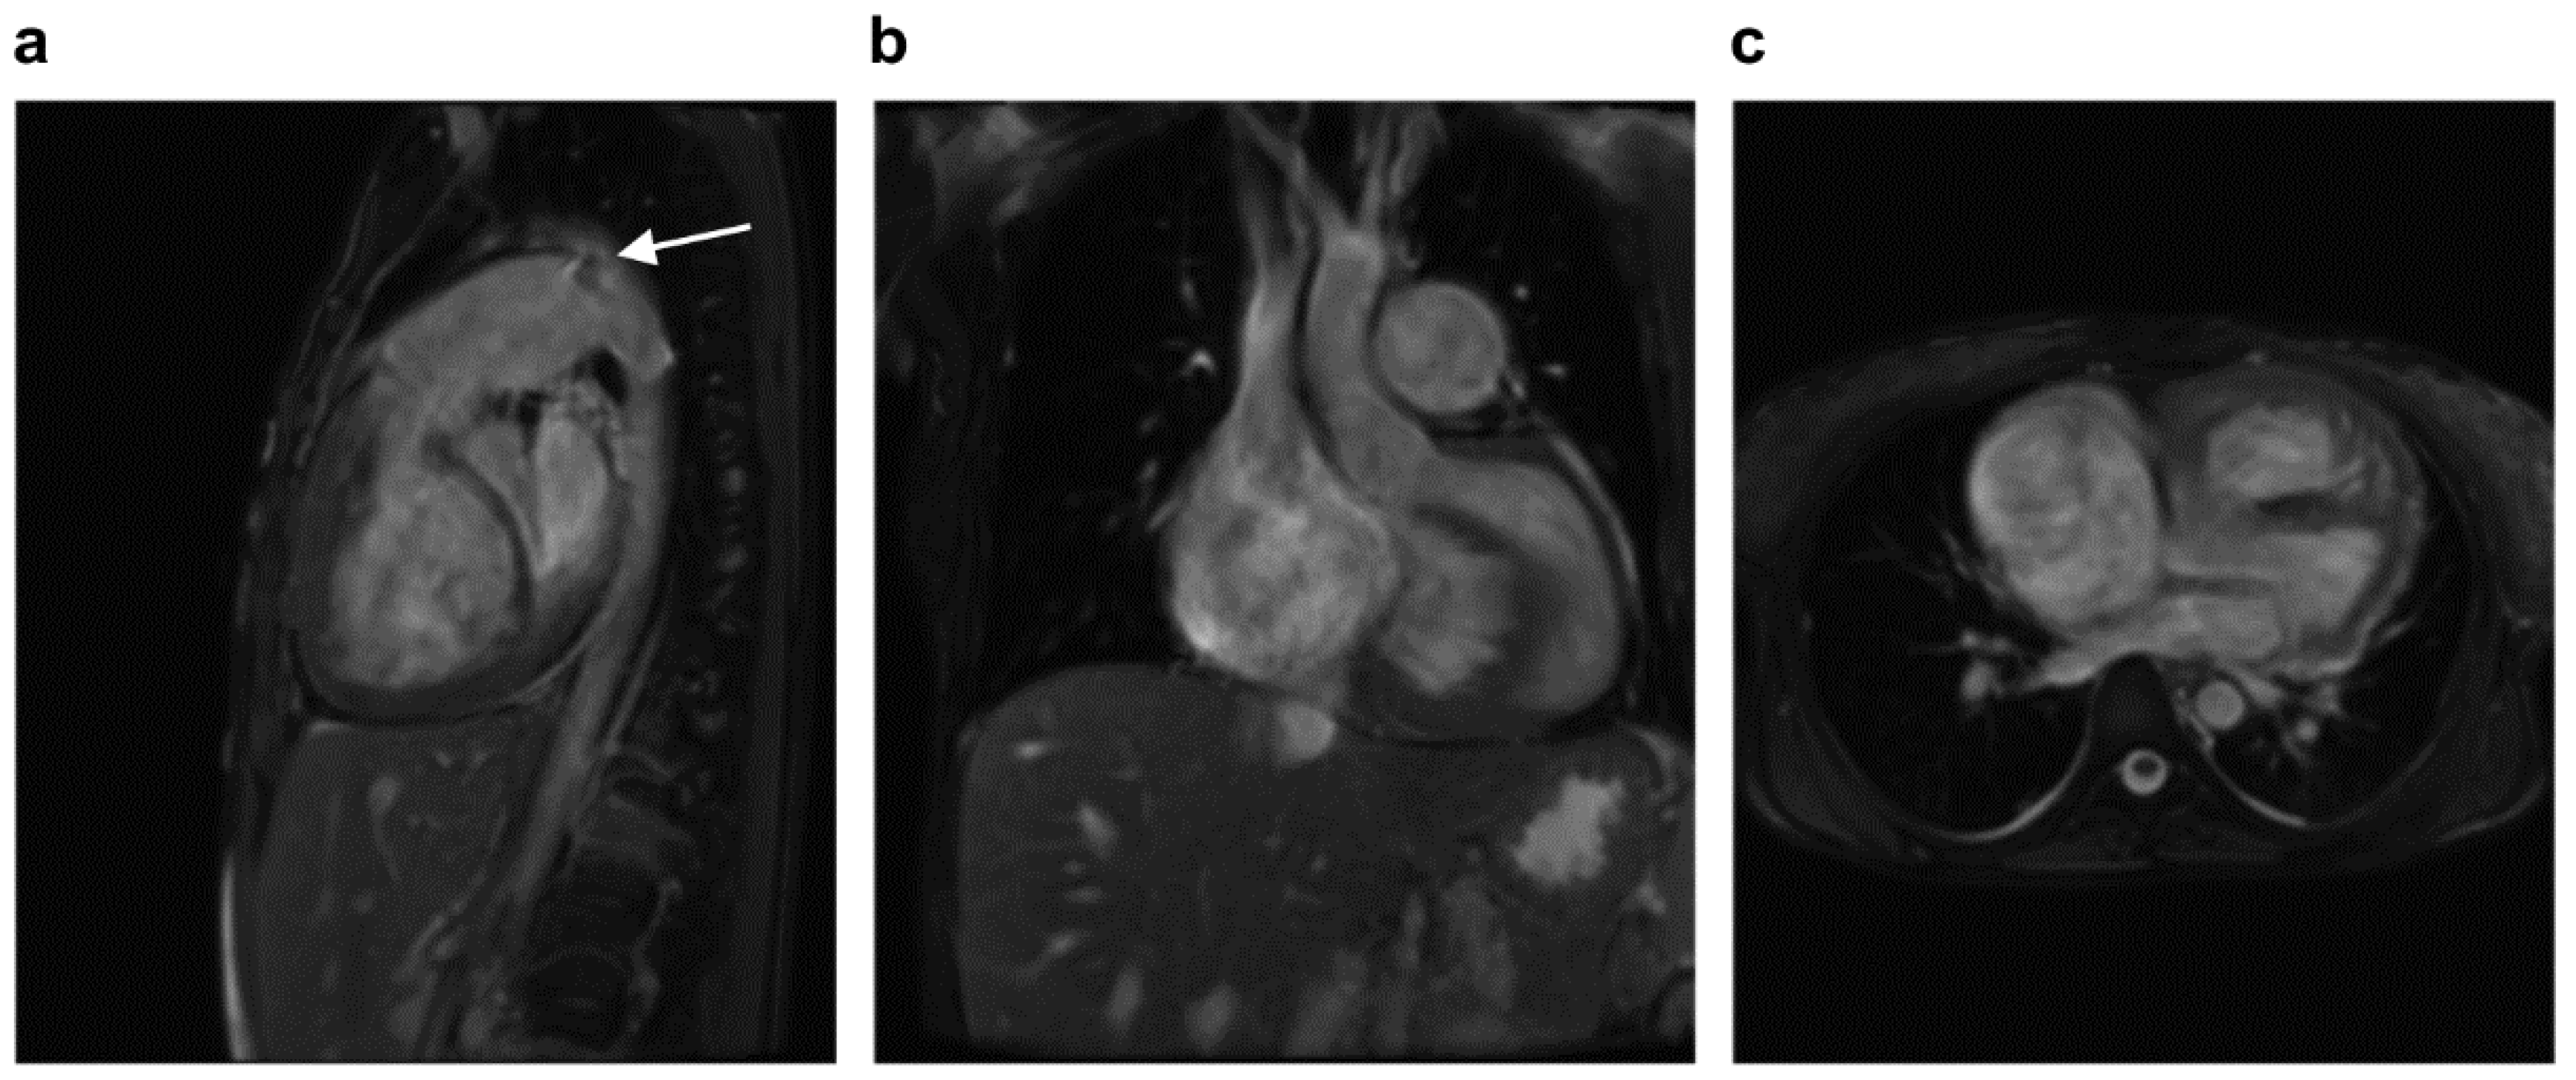

2.1. Case 1

2.2. Case 2